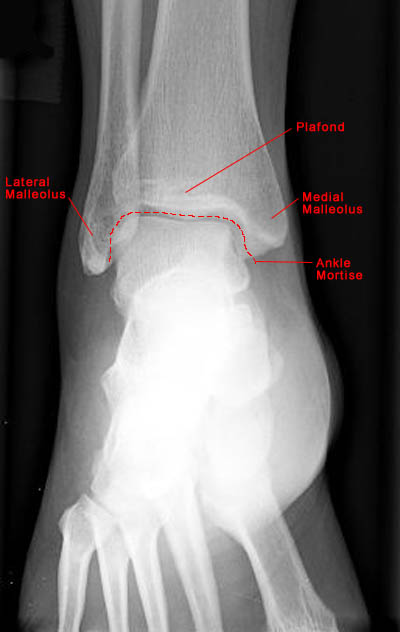

AP View of Normal Ankle

• The ankle joint includes articulations between three structures: tibia, fibula and talus.

• The lateral malleolus is longer than the medial malleolus, a characteristic important for joint stability.

• Standard radiographic examination of the ankle includes AP, lateral and mortise views of the joint.